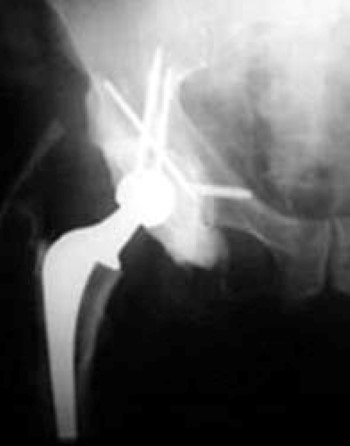

special hip replacement for metastatic bone disease

A 57-year-old man with metastatic kidney cancer and progressive right hip pain requiring a special form of total hip replacement.

Reproduced with permission from Weber K, Lewis V, Randall RL, Lee AK, Spingfield D: An approach to the management of the patient with metastatic bone disease, in Helfet DL, Greene WB (eds): Instructional Course Lectures, Volume 53. Rosemont, IL, American Academy of Orthopaedic Surgeons, 2004.